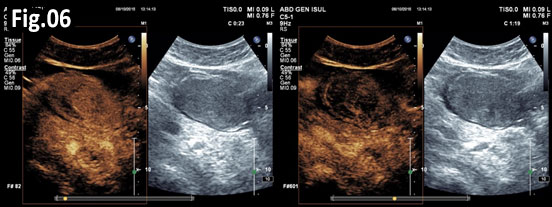

GISTs are rare mesenchymal neoplasms of the digestive tract [1,2]. They have been documented in all parts of the gastrointestinal tract, but are most common in the stomach and small intestine, followed by colo-rectum, mesentery, and esophagus [1,2]. However, the synchronous occurrence of lung cancer and GIST is extremely rare [3]. The incidence of GIST coexisting with additional malignancies is 9% to 27%, and primary lung cancer in GIST patients is 0.5%-1.2% [3]. A 75 year old woman with a smoking history for >30 years was diagnosed with advanced stage of left lung primary adenocarcinoma by chest computed tomography (CT) and bronchoscopy with sampling in February 2015 (Fig.1, Fig.2). The patient started Erlotinib 150 mg/day. In September 2015 the patient was admitted with vague abdominal pain and postprandial vomiting. Physical examination, routine blood, urine and stool investigations were unremarkable. Abdominal ultrasound detected an oval, homogenous, hypoechoic lesion 6/5/4 cm, arising from the submucosal layers of the gastric wall (Fig 3). The color Doppler demonstrated neovascularization (Fig 4). Except for 3 small simple liver cysts, no other abnormalities were present. Upper endoscopy and endoscopic ultrasound (EUS) revealed a large oval, slightly lobulated mass, hypoechoic 6x5cm between incisura angulars and greater curvature of the gastric body, originating from the 4th layer of the wall (muscularis propria). The tumor was slightly “dumbbell” shaped, protruding in and outside the stomach lumen, with several irregular hypoechoic zones and micro cysts within, looked encapsulated without infiltration of the surrounding tissues and pathologic abdominal lymph nodes (Fig. 5). A contrast-enhanced ulstrasound (CEUS) and contrast-enhanced computed tomography (CECT) of the abdomen additionally characterized the lesion and excluded liver metastases. (Fig. 6, Fig. 7) Percutaneous true-cut biopsy of the lesion was performed (18G, two separate puncture sites) (Fig 8). The immunohistochemical analysis revealed epithelioid-type GIST, diffusely positive for c-kit (CD117), with a weak focal expression of S-100 (Fig. 9). Due to life expectancy defined by the unresectable advanced lung cancer, the patient was not indicated for resection of the gastric GIST. Imatinib (Glivec) 400 mg/day was started as a “co-therapy” to Erlotinib in November 2015. After 12 months of co-treatment, a good control of both tumors was achieved. CT and abdominal ultrasound showed the gastric lesion was slightly shrunk on therapy, with large central necrosis (Fig. 10). The patient is being followed up.

Figure 6. CEUS: Arterial hyperenhancement and early venous wash-out